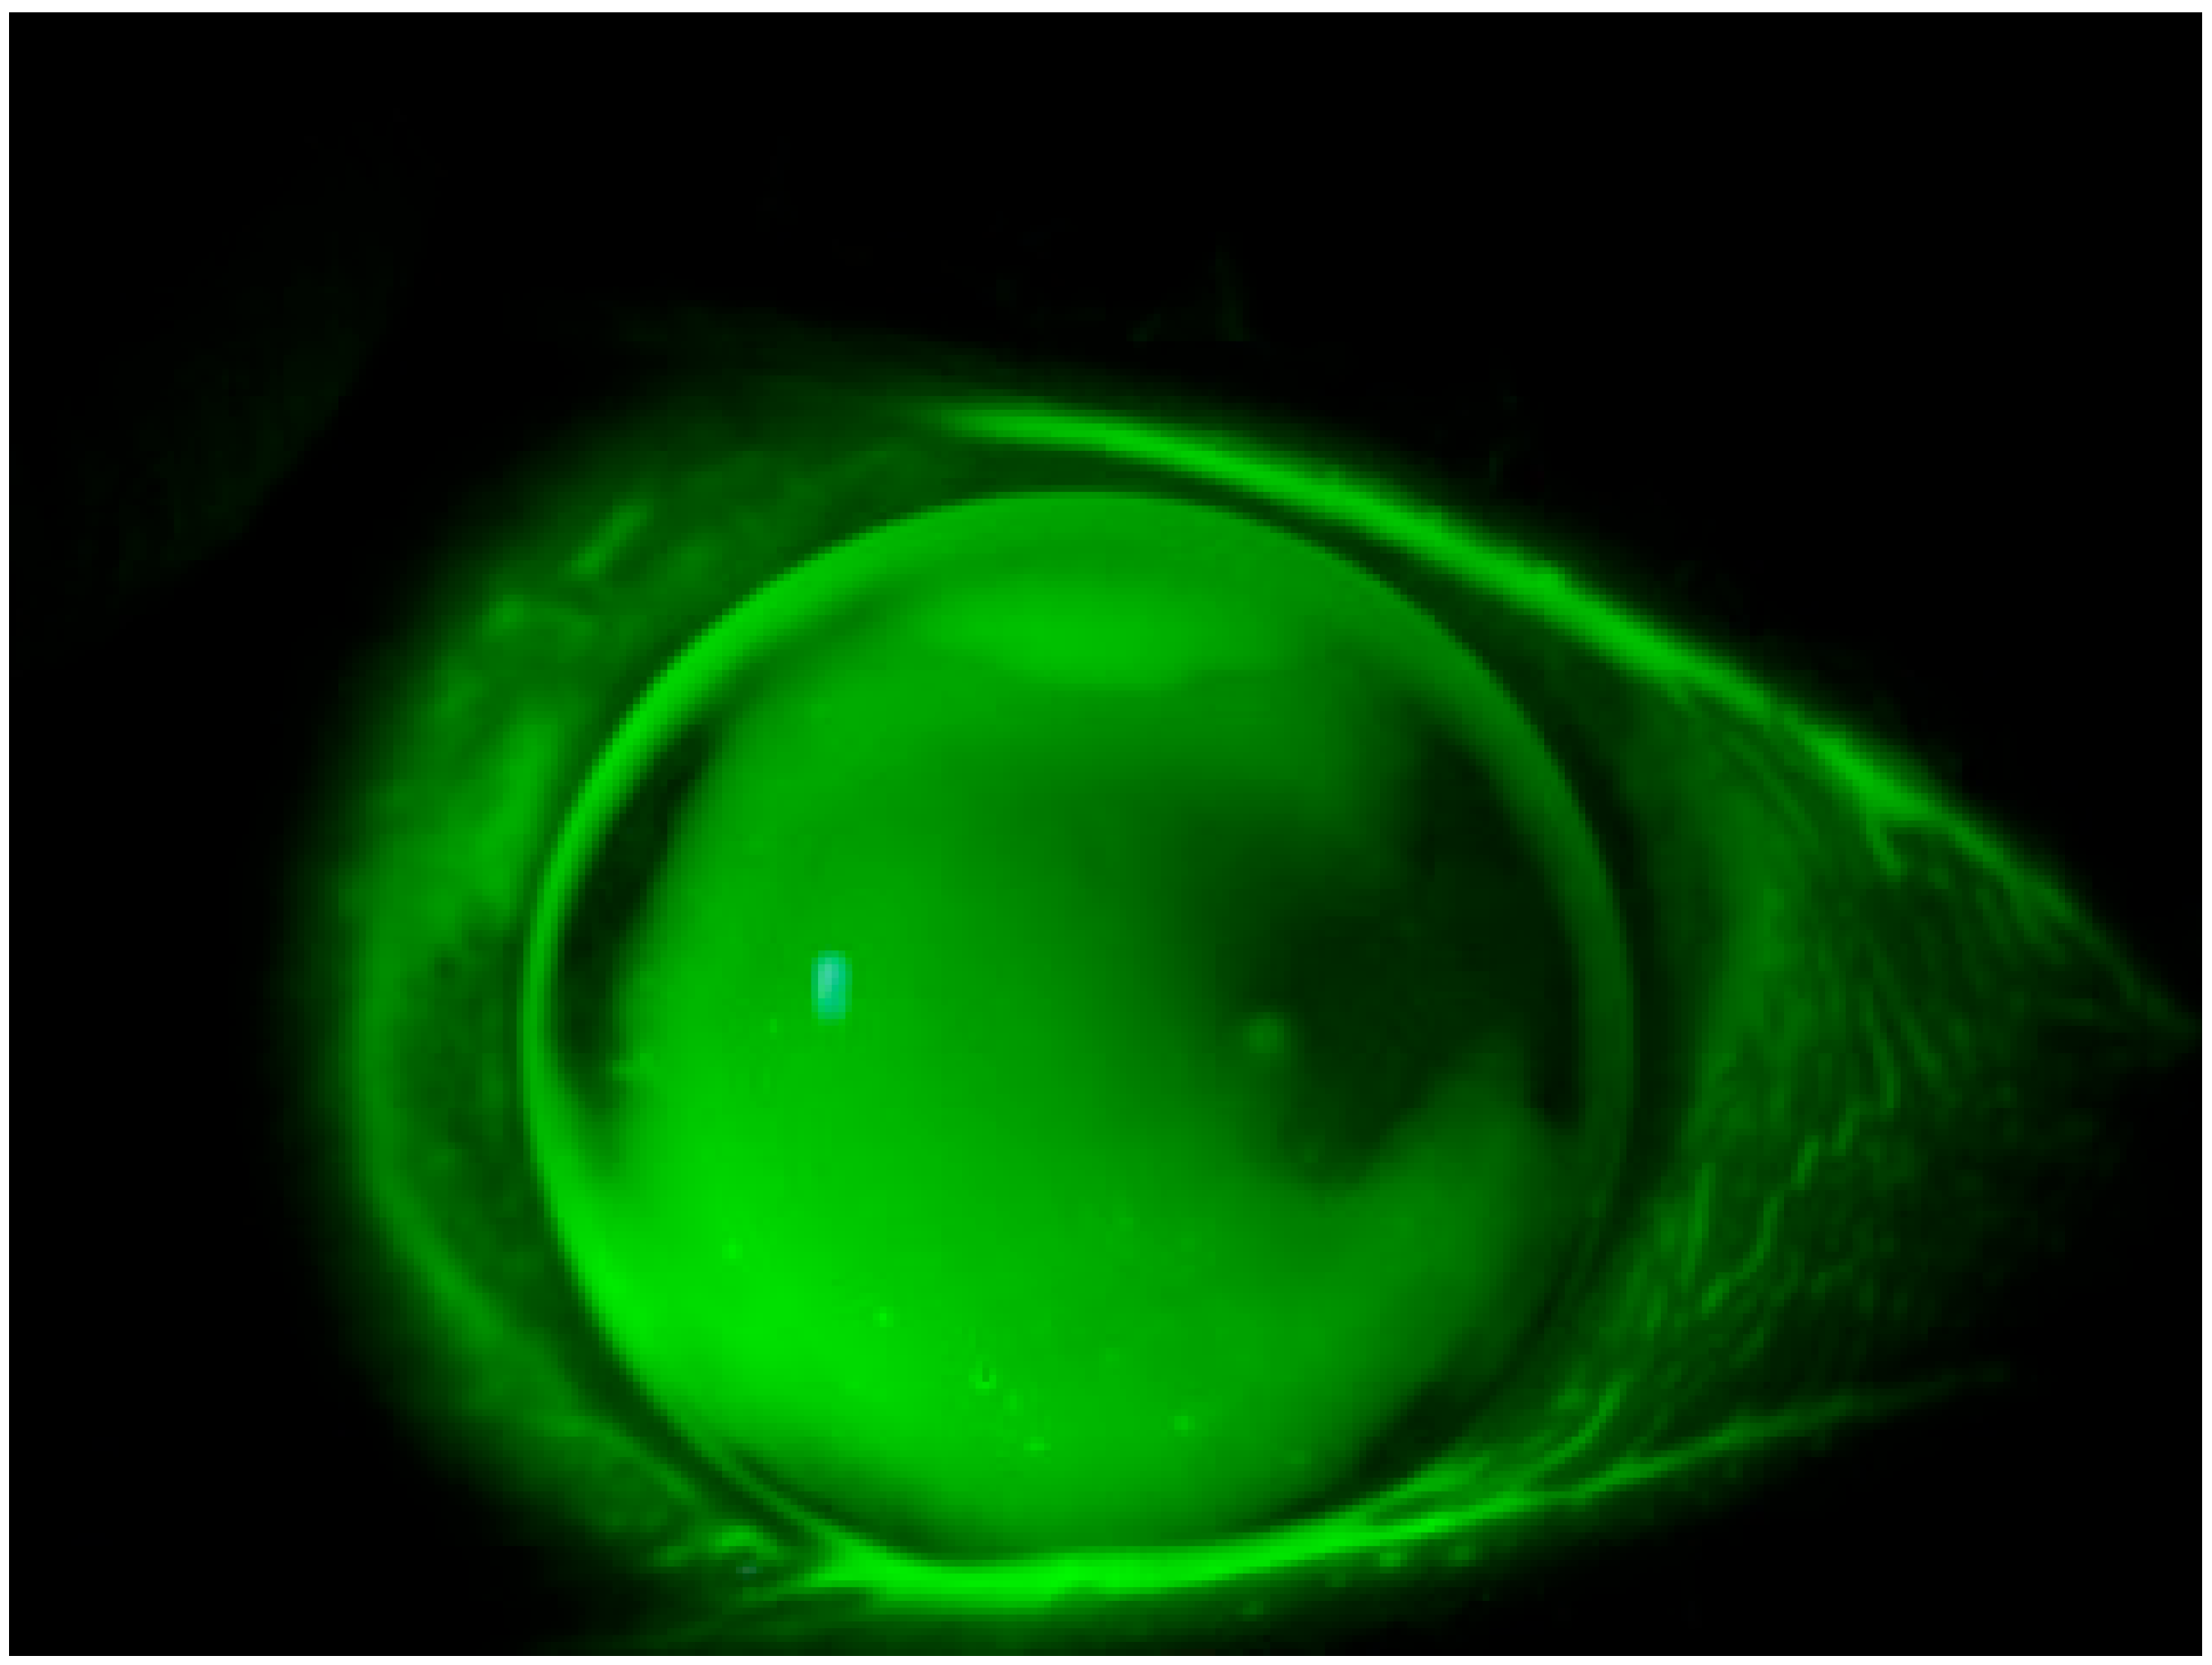

The present study unveils a breakthrough discovery regarding the compatibility of REmark® dye with simultaneous soft hydrogel contact lens wear. This innovative finding demonstrates that soft hydrogel contact lenses efficiently absorb the hydrophilic dye solution, facilitating a comprehensive ocular surface examination without the need for contact lens removal (Figure 1). This novel approach not only overcomes the limitations associated with traditional dyes but also enhances patient comfort and streamlines the diagnostic process.

Moreover, the efficacy of this novel dye in conjunction with a yellow filter for assessing the condition of the bulbar conjunctiva has been investigated, yielding results comparable to those obtained with LG instillation [25,30]. This underscores the versatility and potential of the new dye in comprehensively evaluating changes in both the cornea and conjunctiva, even in the presence of applied soft contact lenses (Figure 2).

Figure 1. Staining with REmark® while keeping the contact lens worn.

Figure 2. Staining with REmark® in the presence of a therapeutic contact lens for filamentous keratitis.